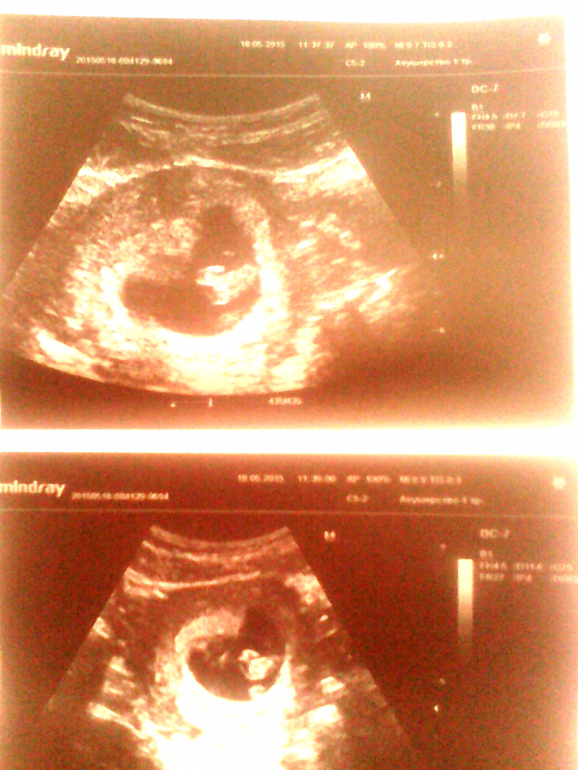

Ну и самое главное-малыш! Он на месте, сердечко колотится, ручки, ножки, головка... Целых 1, 7 см уже! Срок 8-9 недель, получается, что я забеременела точно во время месячных!... Больше никак! Крошка растет. Есть угроза прерывания-тонус передней стенки, у меня и в прошлый раз так было.. Ну просто столько всего происходит... Живот побаливает иногда.

Ну и фотогафии с УЗИ. Малек лежит спинкой вперед.